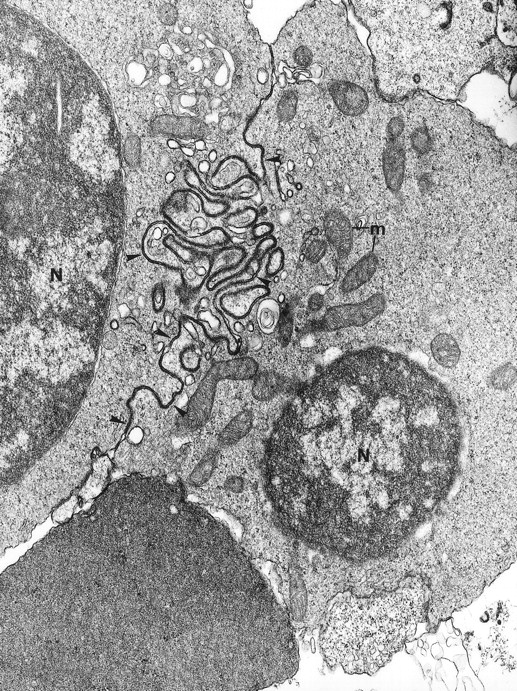

Electron microscopy confirmed the diagnosis of erythroblastic synartesis in the 3 patients. Plasma membranes of adjacent erythroblasts were joined by closely interdigitating processes (Fig2). Cytochemical demonstration of the peroxidatic activity of hemoglobin (not shown) allowed identification of maturation stages of the erythroblasts, because its level of intensity relates to the hemoglobin content of each cell. This technique showed that erythroblasts of the same maturation stage, as well as those of different maturation stages, were linked. Ribosomes were absent at sites of linkage via interdigitating process, corresponding with the nonbasophilic areas observed by light microscopy (Fig3a). At the junction sites, coated pits and rhopheocytosis vesicles were absent, probably because a macrophage expansion would find it impossible to penetrate this zone of tightly linked plasma membrane. Ferritin granules were never observed within these junctions. Junctions between erythroblasts had a characteristic morphology: resembling gap junctions, they were formed by 2 closely placed membranes joined by periodical structures every 150 Å, giving rise to a zipper-like appearance (Fig 3b). Isolated normoblasts often displayed picnotic nuclei and/or binuclearity. The 2 external leaflets of the plasma membrane of adjacent erythroblasts were separated by a constant space of 145 Å in patient 1, and 180 Å in patients 2 and 3.

The electron microscopic aspect of the bone marrow erythroblasts from patient 1: Cells are joined by interdigitating processes of the plasma membrane (arrowheads). They delineate areas of cytoplasm which are deprived of ribosomes (N, nucleus; m, mitochondria). Original magnification: ×21,000.